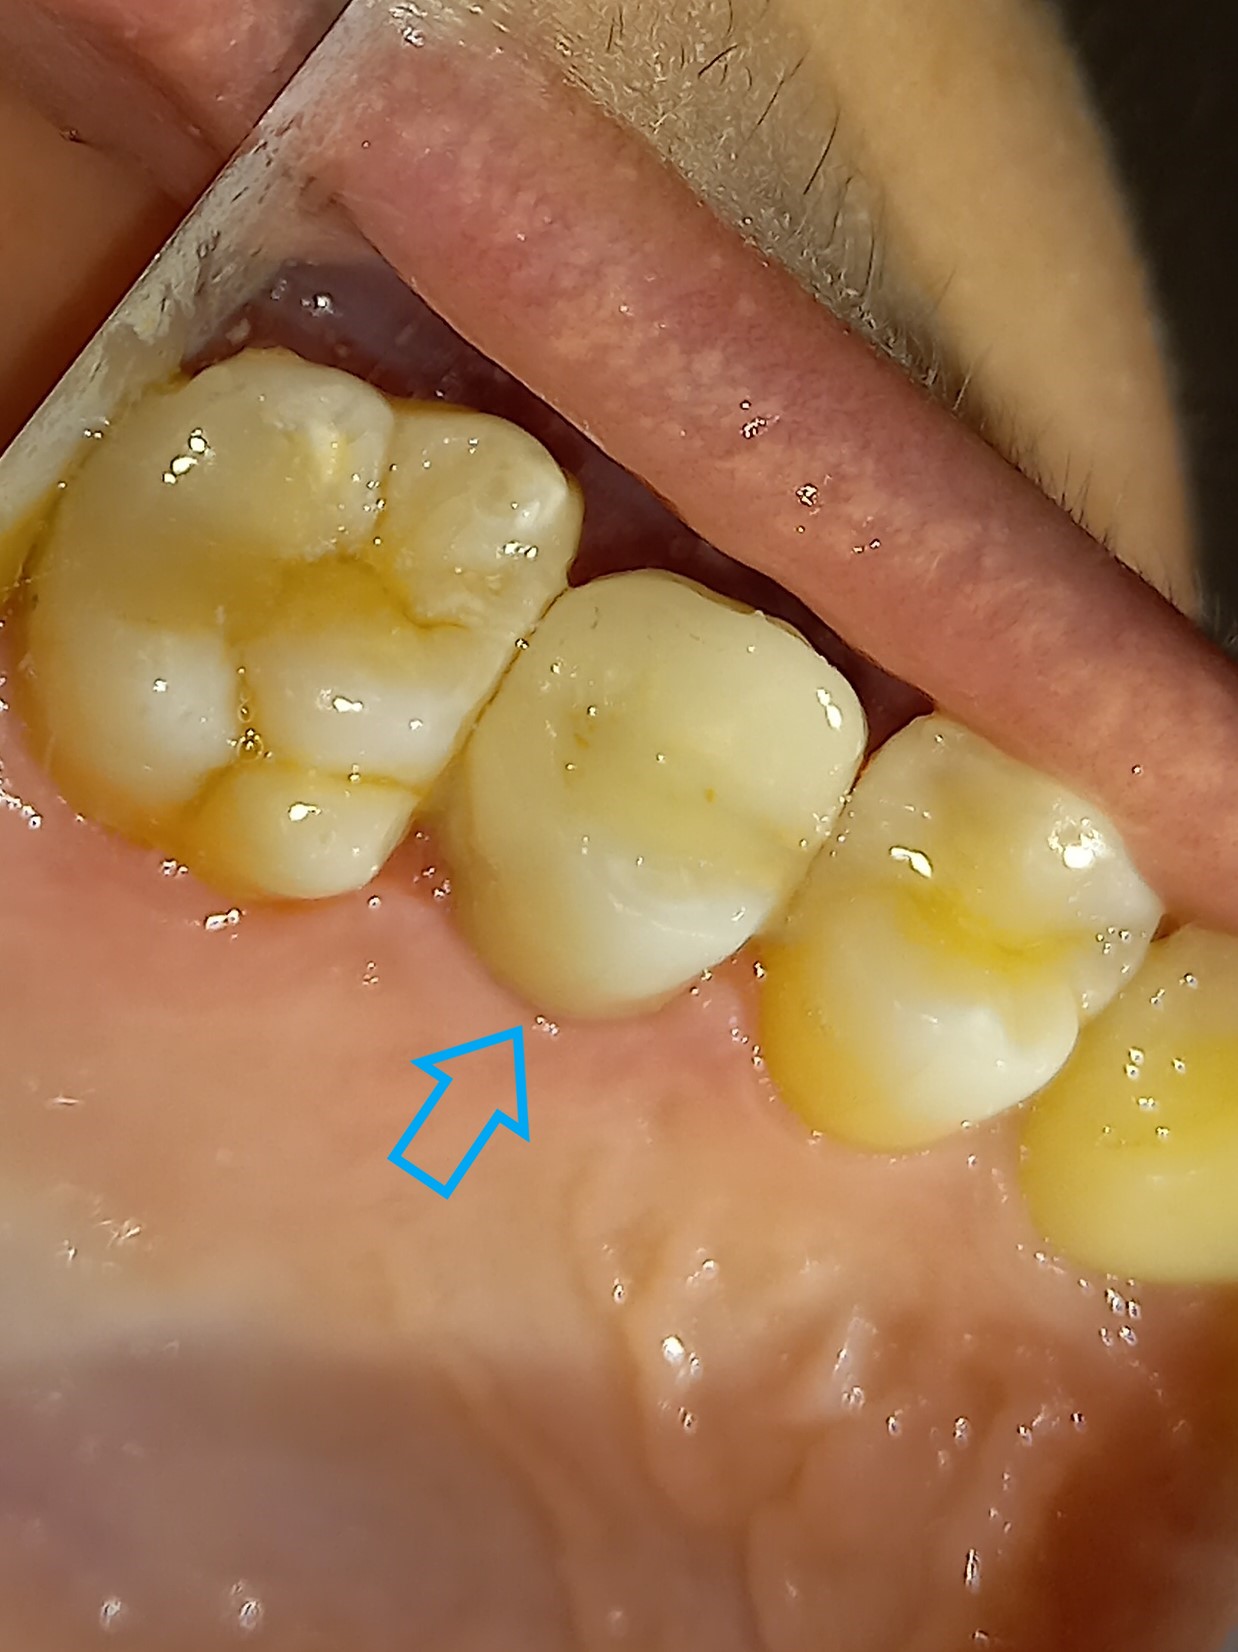

Ο πρώτος γόμφιος στην αριστερή πλευρά της κάτω γνάθου είχε απονευρωθεί στο παρελθόν. Ο ασθενής δεν θέλησε να καλύψει το δόντι με θήκη, ώστε να είναι πλήρως προστατευμένο με αποτέλεσμα το δόντι να σπάσει (όπως φαίνεται στην αρχική εικόνα). Η λύση θεραπείας ήταν η κατασκευή στεφάνης δοντιού, αφού προηγουμένως το δόντι τροχίστηκε καταλλήλως και ο οδοντοτεχνίτης κατασκεύασε την ολοκεραμική θήκη ζιρκονίου.

Το δόντι είναι πλέον πλήρως προστατευμένο και μπορεί να αντέξει στο πέρασμα των χρόνων.

ΠΡΙΝ

ΜΕΤΑ